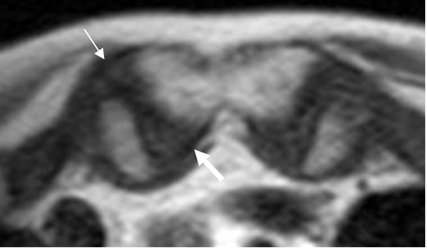

Fig 16. Ligamentos esternoclaviculares.

RM axial en T2. Ligamento esternoclavicular anterior (Flecha delgada) y esternoclavicular posterior (Flecha gruesa).